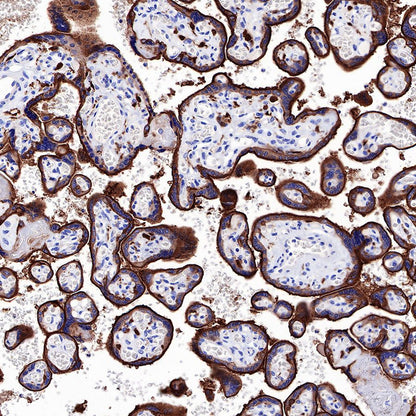

Immunohistochemistry

IHC shows positive staining in paraffin-embedded human placenta. Anti-EGFR antibody was used at 1/2000 dilution, followed by a HRP Polymer for Mouse & Rabbit IgG (ready to use). Counterstained with hematoxylin. Heat mediated antigen retrieval with Tris/EDTA buffer pH9.0 was performed before commencing with IHC staining protocol.